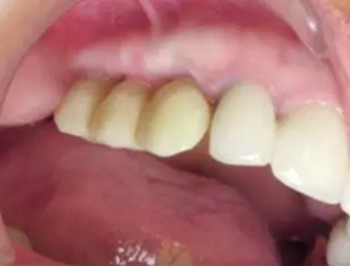

另外,SLA表面可以吸附血漿中的蛋白質(zhì),,并促進(jìn)纖維網(wǎng)狀結(jié)構(gòu)的形成從而加速骨成熟。這對(duì)于拔牙后即刻種植并即刻改善美觀的治療方式來(lái)說(shuō)是一個(gè)巨大的優(yōu)點(diǎn)。術(shù)后10天(圖21)和4周(圖22)復(fù)查,明確牙齦恢復(fù)狀態(tài)和種植體結(jié)合情況。術(shù)后沒(méi)有出現(xiàn)疼痛、水腫或血腫的情況。

圖21

圖22